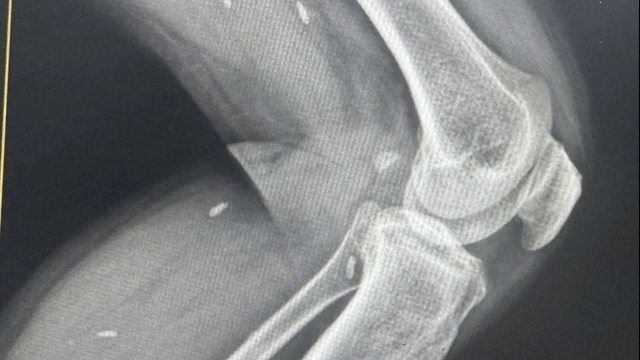

Trong thời gian hoàn thiện các thủ tục hồ sơ bệnh án, khoảng 22h25 phút bệnh nhân xuất hiện đau ngực nhiều và được làm lại điện tim lúc 22h28 phút, có biểu hiện nhồi máu cơ tim. Khoảng 22h30, bệnh nhân đột ngột ngừng tim và được cấp cứu ngừng tuần hoàn trong thời gian 01h30 phút nhưng không thành công. Bệnh nhân tử vong lúc 0h ngày 20/7.

Chẩn đoán tử vong là do ngừng tuần hoàn do nhồi máu cơ tim cấp/suy thận mạn giai đoạn cuối đang chạy thận chu kỳ.